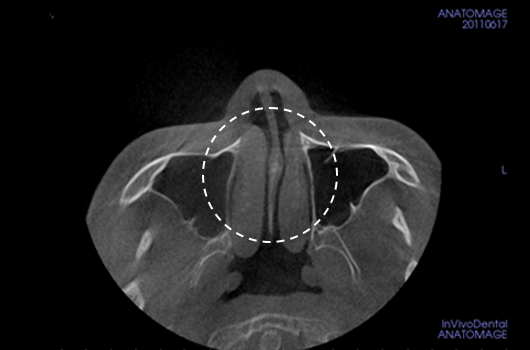

Operasi hidung CT 3D membantu pelaksanaan operasi hidung yang lebih canggih setelah menganalisis wajah secara cermat untuk menentukan mana yang terbaik.Analisis tiga dimensi digunakan untuk mengetahui keadaan secara umum, ukuran, bentuk, dan asimetri tulang hidung, tulang rawan septum hidung, dan jaringan kulit, yang tidak dapat ditentukan melalui konsultasi pada umumnya. Saat merencanakan revisi operasi hidung, kami dapat memeriksa elemen fungsional seperti deviasi septum hidung, bentuk implan yang ada, termasuk implan silikon, atau komplikasi dari operasi sebelumnya.

Melalui 3D-CT scan, tulang dan tulang rawan serta lokasi pembedahan, termasuk apakah dibutuhkannya osteotomi dan seberapa banyak reduksi tulang hidung yang harus dilakukan dapat diketahui.

Pentingnya 3D-CT Scan pada Operasi Hidung

Dalam setiap konsultasi operasi hidung, Klinik Operasi Plastik Braun menggunakan 3D-CT scan untuk menganalisis isu-isu berikut dalam tiga dimensi: Rancangan bedah dapat dibuat lebih tepat dan potensi efek samping dapat berkurang dengan memahami lebih lanjut ukuran, bentuk, dan asimetri bagian hidung yang tak kasat mata dan struktur anatomi disekitarnya sebelum operasi.

Dengan implan yang dibuat khusus untuk setiap pasien dengan bantuan 3D-CT scan, kami dapat mengurangi kemungkinan efek samping dan bisa mendapatkan penampilan yang lebih alami.

1. Analisis tulang rawan septum dalam berbagai ukuran dan bentuk

2. Diagnosis dan tindakan untuk deviasi hidung dan deviasi septal

3. Analisis untuk lebar dan asimetri tulang hidung

4. Diagnosis Inferior turbinate asymametry dan pembedahan hidung tersumbat